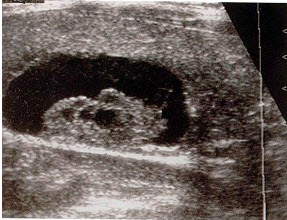

某患者脾脏声像图表现如图,诊断为()